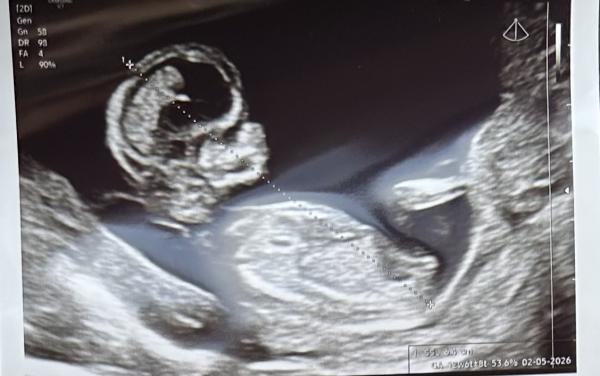

Hallo zusammen, ich bin ganz neugierig darauf zu erfahren welches Geschlecht unser zweites Wunder hat 😊 Meine Ärztin sagt der NUB ist wohl noch sehr neutral weder nach oben noch nach unten gerichtet.. ich weiß nur nicht ob sie einfach noch nicht ihre Tendenz verraten möchte😄   Was denkt ihr von den Bildern her?  Mädchen oder Junge?

Bild zu Nun - Theorie / Geschlecht? - Schwanger - wer noch? Rund um die Schwangerschaft